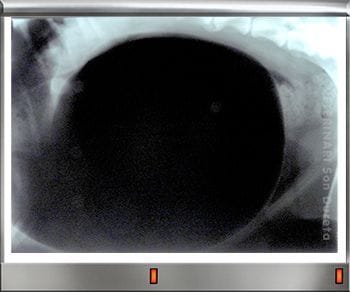

Uno de los síntomas más claros de la torsión gástrica es la gran hinchazón que se produce en el estómago por los gases acumulados, como vemos en este cachorro de Fila brasileiro